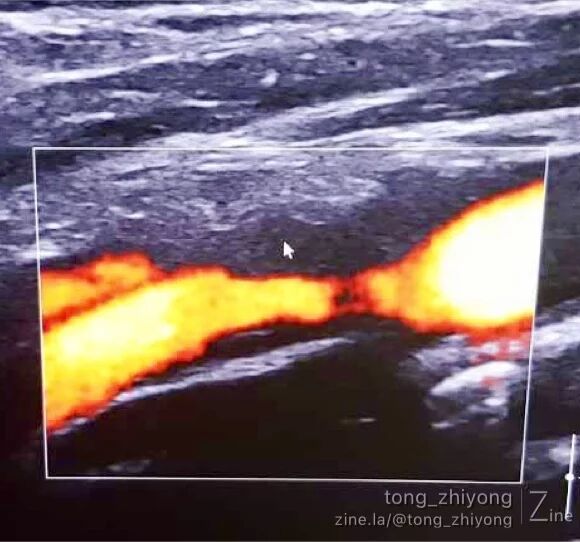

术后一周超声可见:颈总动脉、颈动脉分叉部及颈内动脉近段彩色血流充盈良好,未见明显涡流信号。

术后一周超声可见:颈内动脉近段彩色血流充盈良好,未见涡流。